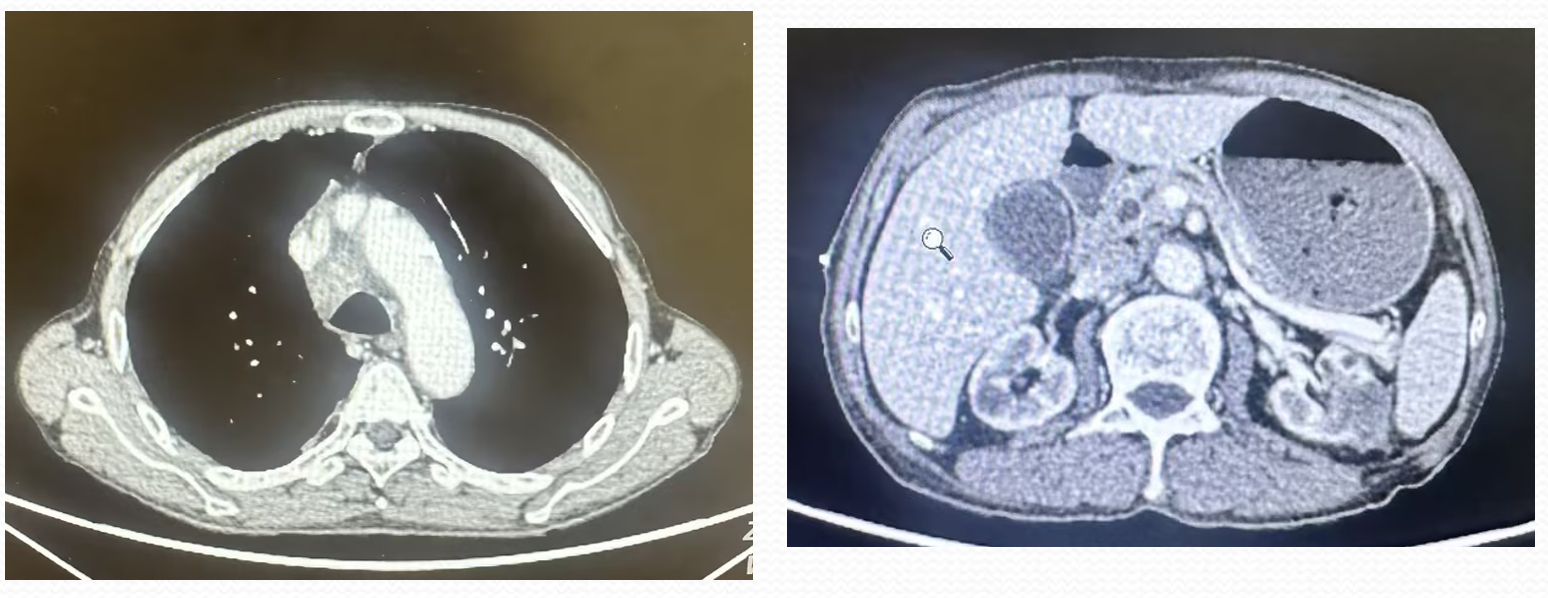

• 2025-9-16胸腹部CT示:1.临床提示左肾肿瘤术后:目前左腹壁瘢痕影、瘢痕处强化不均,左肾上份稍低密度团块影,考虑肿瘤性病变,复发?其它?邻近左侧腹膜后强化结节影,转移?纵隔、右肺门、腹膜后增大、部分坏死,考虑转移;双肺多发小结节,部分转移可能。请结合;临床及外院旧片。2.右侧液气胸、肺组织压缩约40%,右侧胸腔置管影,右肺部分受压不张、强化尚均,合并其它待排;建议治疗后复查。3.肺气肿,双肺散在炎变、部分为慢性炎变。4.主动脉及冠状动脉壁钙化,气管内少许粘液。5.双侧胸膜增厚,左侧胸腔少量积液。6.肝右后叶小囊性灶,建议随诊。7.胆囊结石。8.双肾髮肿。9.前列腺强化不均,必要时结合MR平扫及增强检查。

• 2025年9月22日 免疫组化报告间皮样细胞免疫表型:PAX8(+)、PAX2(一);病理诊断:结合临床及两轮免疫表型,符合“肾癌”转移。

左肾乳头状肾细胞癌I型(含少许透明细胞)伴腹壁、纵隔、腹膜后淋巴结、胸膜、肺转移(rT1N1M1 IV期)。慢性肾脏病4期;高血压1级 高危;中度贫血。

• 2025-9-30行洛铂+地塞米松控制胸水,具体:地塞米松10mg及洛铂10mg胸腔灌注,胸腔灌注后拔除胸腔穿刺引流管。并口服培唑帕尼片800mg qd靶向治疗。

• 治疗 20 多天后患者出现气急、腹泻等症状,暂停培唑帕尼治疗,复查 CT 显示部分病灶缩小,但心包积液增多,行心包腔及双侧胸腔穿刺引流,病理提示心包转移,给予洛铂及地塞米松心包腔灌注,